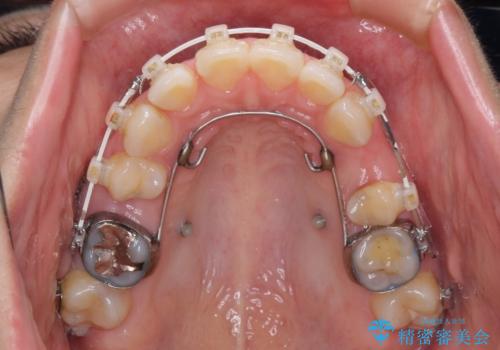

- 矯正装置

- 審美装置

口元を積極的に引っ込めるために、上下左右の小臼歯計4本を抜歯することとしました。

セオリーでは第一小臼歯を抜歯しますが、上下右側は第二小臼歯に銀歯が装着されているため、第二小臼歯を抜歯することとしました。

上下正中を左右対称に揃えるため、アンカースクリューや補助装置を使用しながら口元を下げていくこととしました。

積極的に前歯を牽引したことで、口元の閉じにくさは顕著に改善され、横顔のシルエットが大幅に変化しました。